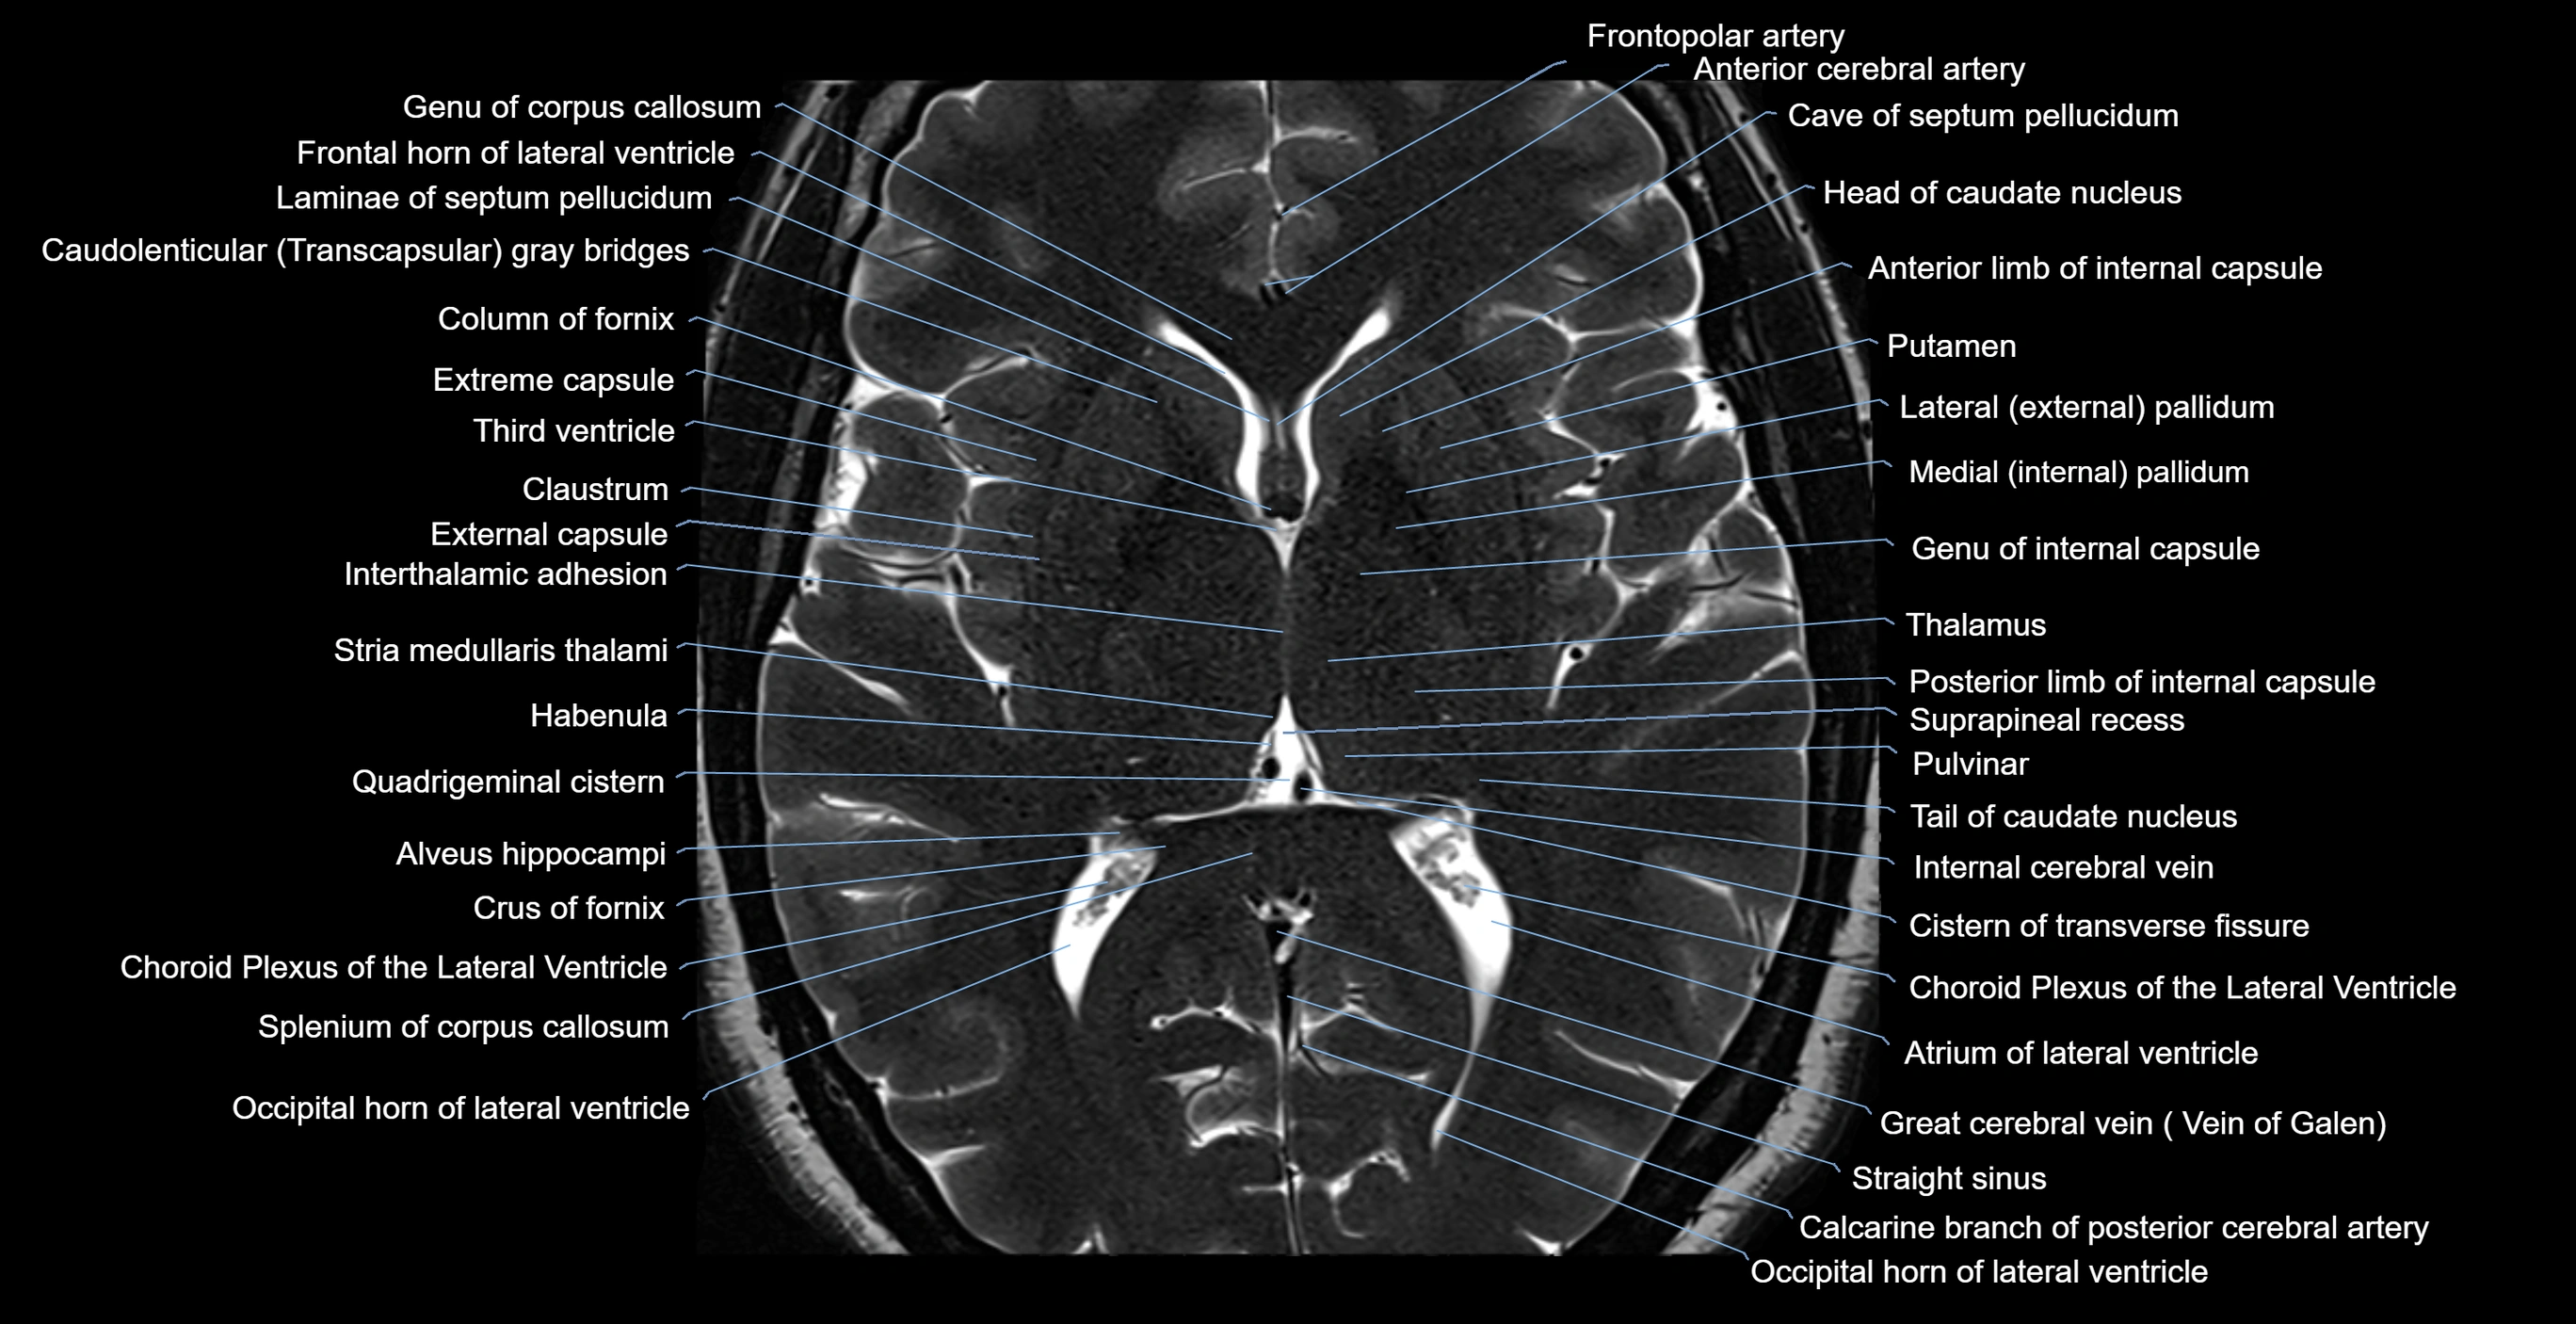

MRI images